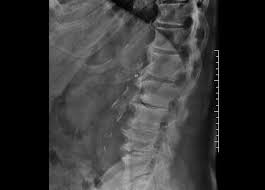

Redução do espaço discal L1 _ L2. Paciente deve trazer todos os exames de imagem realizados anteriormente.

Coluna lombar - perfil em extensÃo mÁxima Paciente Em decúbito lateral ortostático PMS paralelo à LCELCM posicionar de modo que a coluna lombar fique sobre esta linha fazer a extensão ao máximo do paciente forçando ombros e quadris para trás os membros superiores na cabeça ou para atras. Rx de Coluna Inteira. RX Coluna Lombar APPerfilL5S1 Em breve você realizará o exame de RX que visa avaliar ossos e estruturas. Rx de coluna cervical dorsal e lombar para escoliose. Têm uma Smart Fit te esperando agora mesmo. O exame é contraindicado para gestantes salvo em situações nas quais absolutamente. Em casos de RX com contraste poderemos necessitar de punção venosa ou sondagem a depender da indicação e avaliação prévia pela equipe responsável. Não é possível identificar hérnias de disco com esse exame. RX COLUNA DORSO LOMBAR PARA ESCOLIOSE.

PREPARO Chegar 20 minutos antes do horário marcado. Rx da Coluna Lombar - APPERFIL. RX Coluna Lombar APPerfilL5S1 Em breve você realizará o exame de RX que visa avaliar ossos e estruturas. RX DE COLUNA LOMBAR FRENTE E PERFIL PERFIL DO SACRO PARA QUE O EXAME SEJA REALIZADO O PACIENTE DEVE. I - Informações sobre o exame - Trata-se de exame de raios X da coluna lombossacra em flexão e extensão. Obviamente isso não significa que outras causas potenciais de dor lombar não justifiquem imagens médicas imediatamente ou posteriormente. Não perca a chance de treinar na maior rede de academias da América Latina.